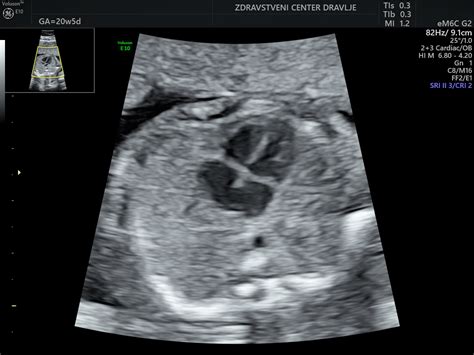

V 24. tednu nosečnosti otrok meri od temena do trtice približno 21 cm in je primerljiv s koruznim klasom, le da je težji. Njegovo telo je že skoraj popolnoma oblikovano, čeprav je še vedno nekoliko suhceno in se bo v naslednjih tednih še dodatno okrepilo. V otrokovih pljučih se začenja nastajati snov, imenovana surfaktant, ključna za ohranjanje odprtih drobnih zračnih mešičkov (alveol) v pljučih, kar mu bo omogočilo dihanje po rojstvu. Otrok že vadi dihanje, kar je začel že okoli 17. tedna. Zaradi svoje velikosti pa bo nekoliko omejil svoje akrobatske vaje v maternici.

Koža vašega dojenčka je v tem tednu tanka, prosojna in nagubana, vendar pa je že povsem razvita. Pričenja kopičiti rjavo maščevje v predelu podkožja na hrbtu in lopaticah. Možgani mu hitro rastejo in brbončice morebiti že delujejo. V pljučih se mu razvijajo veje dihalnega drevesa in celice, ki proizvajajo površinsko aktivno snov, ki omogoča enostavno napihovanje zračnih mešičkov. Otrok sedaj že lahko odpre in zapre oči, lahko brca, sesa palec, odpira in zapira usta ter se odziva na premikanje ali glasne zvoke. Obdaja ga približno pol litra tople plodovnice, v maternici pa je dovolj prostora, da se prekopicava in obrača.